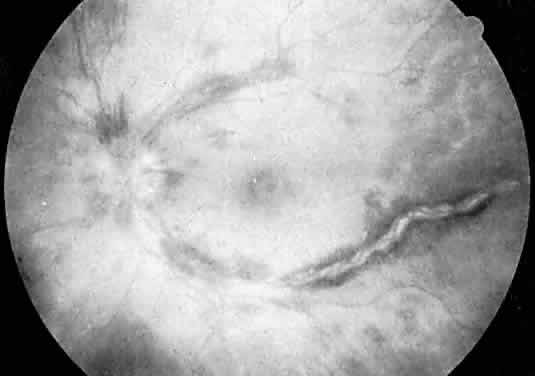

Although ocular and periocular hemorrhages may occur, particularly after trauma or surgery, ocular manifestations of hemophilia are primarily neuro-ophthalmologic in nature, resulting from CNS hemorrhage. Pupillary abnormalities, cranial nerve palsies, visual blurring, and papilledema have been described after intracranial bleeding.2,3 Repeated retinal hemorrhages and vitreous hemorrhage have been associated with factor IX deficiency.4,5